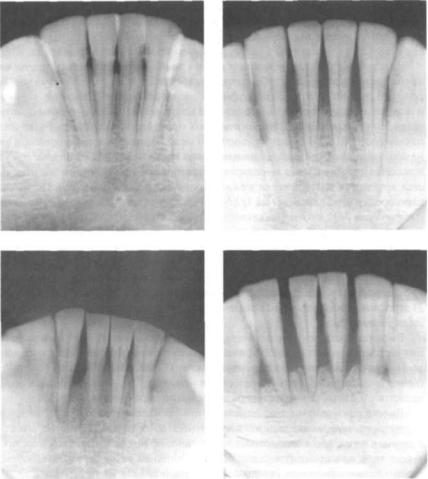

Анатомия: Межкорневая костная перегородка

Раздел: Галерея впечатлений